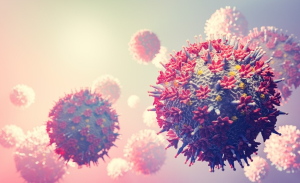

Pseudomonas aeruginosa: o que é a bactéria encontrada em lote de água Crystal e em produtos da Ypê

Embora seja considerada uma bactéria comum no ambiente e raramente represente risco para pessoas saudáveis, a Pseudomonas aeruginosa é conhecida por causar infecções oportunistas em indivíduos com o sistema imunológico comprometido.

A bactéria Pseudomonas aeruginosa voltou a ser motivo de preocupação de saúde pública após aparecer em dois episódios recentes de recolhimento de produtos no Brasil. Nesta quarta-feira (3), a Agência Nacional de Vigilância Sanitária (Anvisa) determinou o recolhimento de um lote da água mineral Crystal após análises laboratoriais confirmarem a presença do microrganismo.

Meses antes, a mesma bactéria havia sido identificada em lotes de produtos da Ypê, levando a empresa a realizar um recolhimento voluntário e, posteriormente, motivando medidas mais amplas de fiscalização por parte da agência reguladora.

Embora seja considerada uma bactéria comum no ambiente e raramente represente risco para pessoas saudáveis, a Pseudomonas aeruginosa é conhecida por causar infecções oportunistas em indivíduos com o sistema imunológico comprometido.

Entenda a seguir o que é esse microrganismo, onde ele costuma ser encontrado e por que sua presença em produtos destinados ao consumo ou uso doméstico desperta preocupação das autoridades sanitárias.

O que é a bactéria?

A Pseudomonas aeruginosa é um microrganismo comum no ambiente. Está presente no ar, na água, no solo e pode ser encontrado inclusive na pele de pessoas saudáveis. Ela é classificada na literatura médica como uma bactéria oportunista: raramente causa infecção em pessoas saudáveis, mas pode provocar ou agravar quadros infecciosos em pessoas com o sistema imunológico comprometido.

É justamente esse perfil que explica a preocupação com imunossuprimidos, cuidadores e profissionais de saúde.

De acordo com o Manual MSD, referência em informações médicas, "essas bactérias são favorecidas por áreas úmidas, como lavatórios, sanitários, banheiras de hidromassagem e piscinas com cloro inadequado, e soluções antissépticas vencidas ou inativadas. Às vezes, essas bactérias estão presentes nas axilas e na área genital de pessoas saudáveis".

As infecções por Pseudomonas aeruginosa variam de infecções externas pequenas a distúrbios sérios com risco de morte, segundo a MSD.